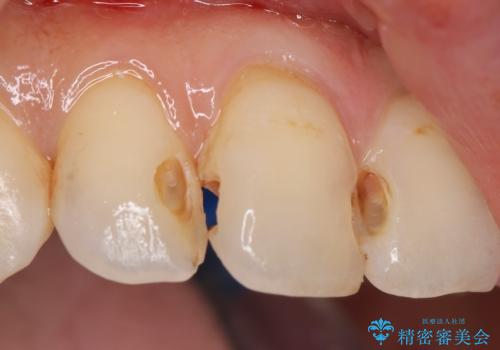

前歯の劣化したコンポジットレジン修復をセラミッククラウンへ

再度レジン修復を行うか、劣化のスピードは遅いが歯の削合が必要なセラミッククラウンの治療の選択肢をご提案し、今後のやりかえの心配の少ないセラミッククラウン治療を希望されました。

- 52.8万円(ジルコニアクラウン×4・仮歯×4)費用は治療当時の料金となります